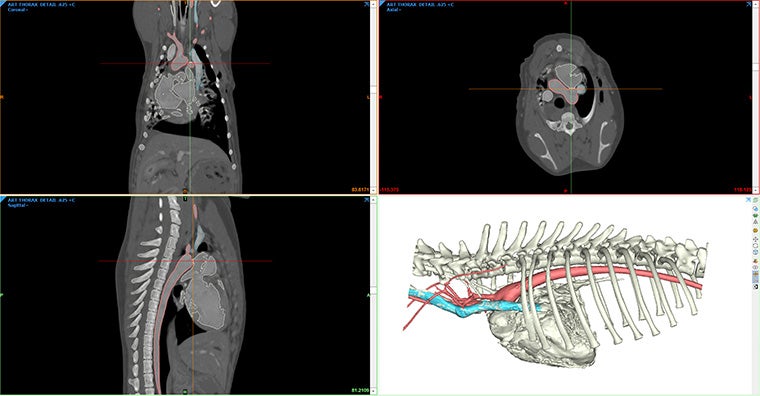

Create detailed, patient-specific 3D models from CT and MRI scans with Mimics. You'll visualize complex anatomical structures with unparalleled accuracy for more precise and effective surgical interventions.

From routine procedures to advanced surgeries like maxillofacial reconstructions, this versatile tool supports a wide range of veterinary applications.